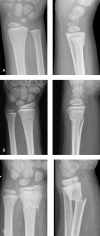

Figure 2.

Primary radiographs of 3 different metaphyseal fractures, demonstrating the difference in cortical involvement in buckle (A), greenstick (B), and complete (C) fractures. A. Buckle fracture in a 7-year-old girl. B. Greenstick fracture in an 8-year-old girl. C. Complete fracture in a 7-year-old boy.